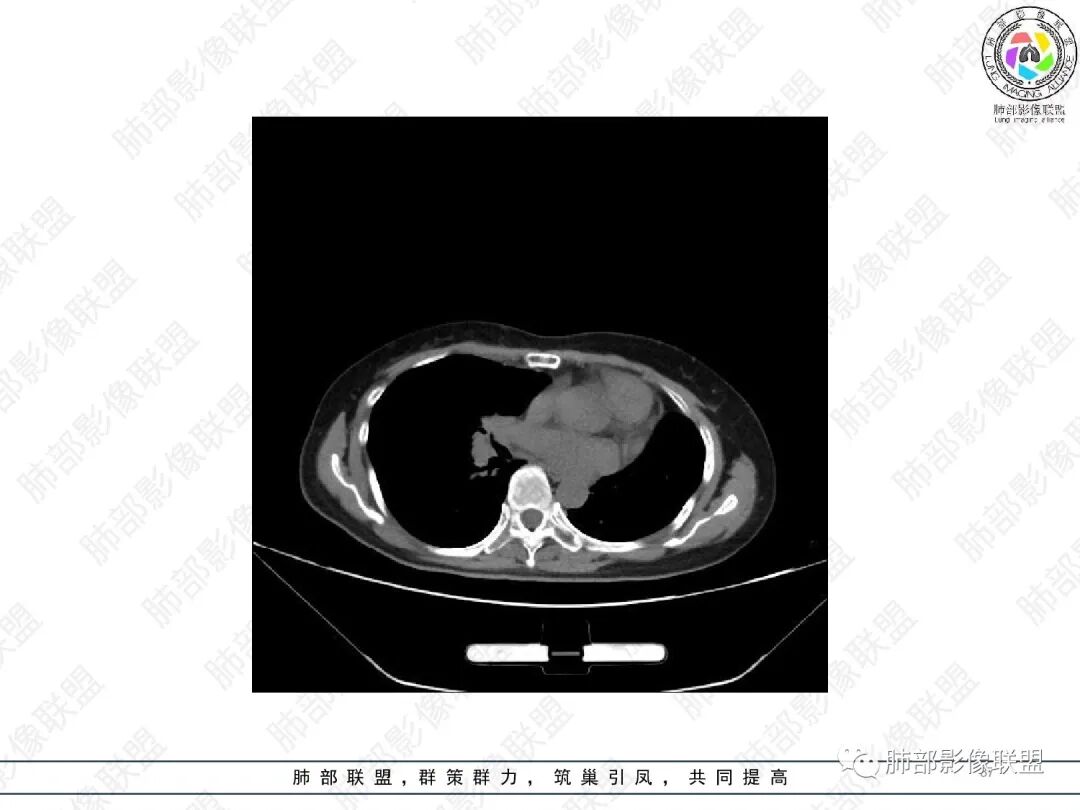

2.胸部CT:右肺上叶及中叶不规则块状影,沿支气管走行方向指套样影,支气阻塞湖嵌塞,腔内可见高密度影。灶周可见磨玻璃,外围见结节影及树芽征。左肺体积缩小,见不规则条索影、胸膜增厚,纵隔牵拉左移。

3.综合分析:结合患者病史及胸部CT主要鉴别ABPA(右肺上叶不规则块影,指套样顺延支气管方向,抗结核治疗1年,肺部病灶仍明显)及继发性肺结核TB(右肺上叶不规则肿块,其可见高密影,边缘模糊,周围卫星灶、树芽征,沿支气管爬行)。